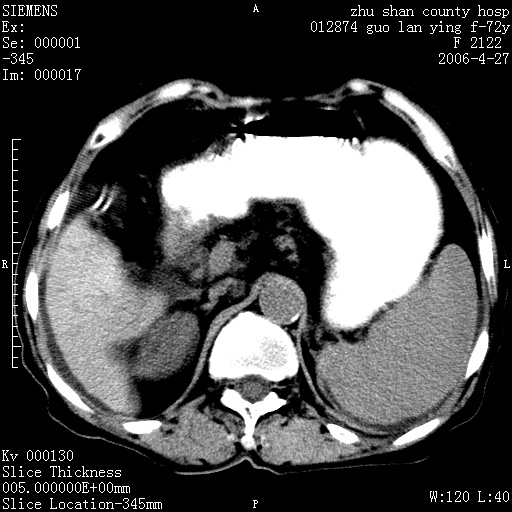

平扫所见:胆囊区两点壮高密度影,灶周有伪影{请问楼主患者有手术病史?}。肝实质内未见明显异常{建议强化或mri}.腹腔有少量积液,脾明显增大.右肾形态似不规则?

腹腔内示积液征,脾脏略增大,肝脏由于运动伪影较多,影响观察,内未见明显高密度区,胆囊内示两处高密度结石。胃窦部壁轻度增厚。另外,肝脏的前缘似有游历气体。不知病人的临床如何?有必要做胃的检查,还有,看看骨窗是否有腹腔游离气体还是肠管影响的。

肝脏缩小,脾脏增大,肝脾外缘及胆囊窝液性密度影,肝脾ct值正常,胆囊区见两个类圆形高密度影,下腔静脉前方类圆形软组织密度影为肝脏岛叶,胃幽门区见软组织密度影,十二指肠钡剂充盈不好.

1:腹水2:胆囊结石3肝硬化?(不确定,请结合临床)4幽门区占位?(建议胃肠透视)

肝硬化,脾大,少量腹水

肝硬化、腹水、脾大,胆囊结石可以肯定。只是肝右叶两个低密度有必要增强确定一下;排除小肝癌。